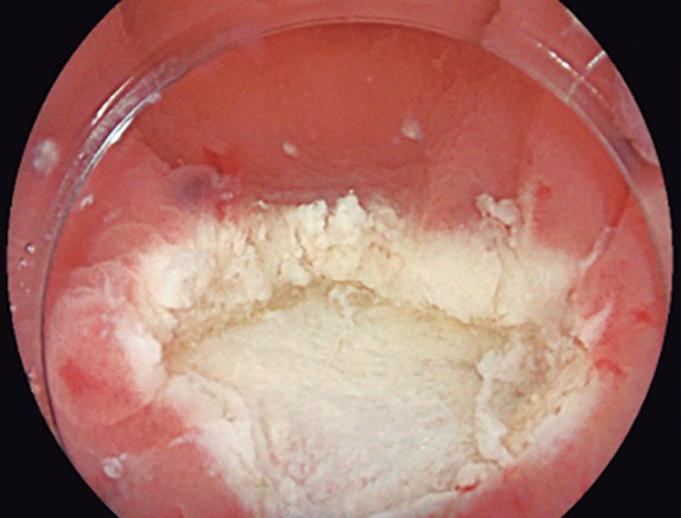

Evaluación endoscópica e histológica

La endoscopía superior es un procedimiento fundamental para el diagnóstico, la evaluación de la respuesta al tratamiento y el monitoreo a largo plazo de la actividad de la EEo. Los hallazgos endoscópicos típicos incluyen edema (reducción de vascularidad), anillos esofágicos fijos, exudados blancos, surcos longitudinales, estenosis, estrechamiento de la luz esofágica, friabilidad de la mucosa (mucosa en papel crepé) y una consistencia firme de la mucosa al realizar biopsias (signo de “tracción" o "resistencia”) en pacientes con fibrosis (Figura 1). Estos hallazgos no son patognomónicos y no constituyen un criterio diagnóstico; sin embargo, cuando se evalúa de forma cuidadosa, en la gran mayoría de los casos se pueden observar.19-21

Un elemento fundamental en la evaluación de la EEo es la aplicación del puntaje de referencia endoscópica para la esofagitis eosinofiílica (EREFS por sus siglas en inglés: Eosinophilic Esophagitis Endoscopic Reference Score).20 El acrónimo EREFS también refleja las cinco características endoscópicas principales de la EEo: Edema, anillos esofágicos (Rings), Exudados, surcos longitudinales (Furrows) y estenosis (Stricture). Estas características se clasifican según su severidad mediante un sistema de puntuación que oscila entre 0 y 9, considerándose la región esofágica con la alteración más marcada. El EREFS cuenta con validación interna y externa, y ha demostrado una elevada capacidad para diferenciar la EEo de otras patologías no relacionadas en poblaciones pediátricas y adultas, además de correlacionarse con la respuesta terapéutica.23-25 Por estos motivos, el EREFS constituye un sistema estandarizado para la evaluación

En el panel A se observa un esófago con edema difuso y pliegues longitudinales; en el panel B se aprecia edema con pliegues y exudados blanquecinos; en el panel C se evidencia un estrechamiento luminal acompañado de anillos esofágicos y exudados; y en el panel D se muestra un desgarro mucoso posterior a la dilatación con bujía de Savary, hallazgo esperado tras este procedimiento terapéutico.

Figura 1. Características endoscópicas de la esofagitis eosinofílica